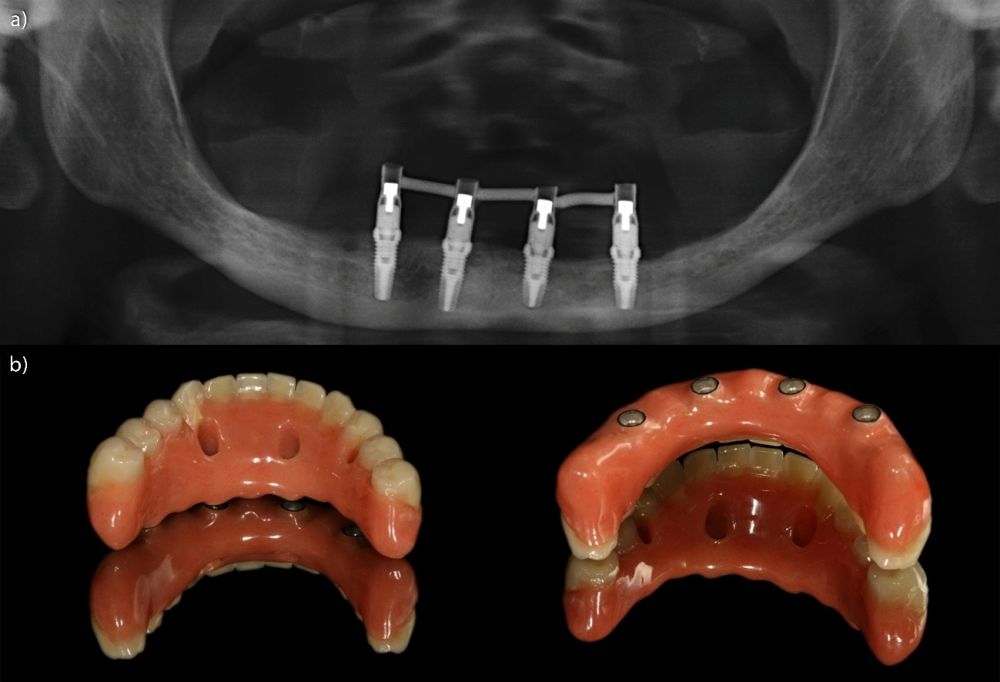

Fueron evaluadas 26 prótesis híbridas mandibulares soportadas por cuatro implantes, lo que genera un total de 104 implantes. De estas 26 prótesis, 12 fueron prótesis sobre implantes cortos (longitud < 10 mm) y 14 como prótesis sobre implantes largos (≥ 10 mm). La muestra presentó un claro predominio femenino, con 21 mujeres (80,8%) y 5 varones (19,2%). La edad media de los pacientes fue de 69,7 ± 11,2 años en el momento del inicio del estudio. A nivel de implante, la densidad media del hueso receptor fue de 866.16 ± 146.35 HU, mientras que el torque medio de inserción alcanzó 47.88 ± 9.01 Ncm. En cuanto a los diámetros de los implantes, en el grupo de los implantes cortos, el más frecuente fue el de 3,5 mm con un 56,5% de los casos, mientras que en el grupo de los implantes largos el diámetro predominante fue para 3,5 y 3,75 mm con un 32,1% para cada una de las categorías (Figura 1.a). En cuanto a la distribución de las longitudes, en el grupo de los implantes cortos, la más frecuente fue 7,5 mm con un 54,3% mientras que en los implantes largos la más frecuente fue 10 mm (47,2%) (Figura 1.b).

Todos los implantes fueron rehabilitados con prótesis híbridas atornilladas, sobre transepitelial. Este transepitelial presentó una altura entre 1 y 4 mm siendo el más frecuente 3 mm en el 75,8% de los casos. La distribución de las alturas de los transepiteliales se muestra en la Figura 2.

El análisis global de los 99 implantes reveló una pérdida ósea marginal media de 0,77 ± 0,26 mm en la superficie mesial y 0,79 ± 0,29 mm en la distal, valores que se mantuvieron dentro de los rangos considerados clínicamente aceptables para rehabilitaciones mandibulares. Cuando los implantes se categorizaron según su longitud, se observaron diferencias claras entre ambos grupos. Los implantes cortos (<10 mm) mostraron una pérdida ósea mesial media de 0,61 ± 0,23 mm y distal de 0,56 ± 0,22 mm, mientras que los implantes largos (≥10 mm) presentaron pérdidas significativamente mayores (mesial: 0,92 ± 0,19 mm; distal: 0,99 ± 0,17 mm). Dado que las pruebas de normalidad (Shapiro–Wilk) mostraron una distribución no normal en todos los grupos (p < 0,001), se aplicó la prueba no paramétrica de Mann–Whitney U. Los resultados confirmaron diferencias estadísticamente significativas tanto en la pérdida ósea mesial (U = 2068,5; p < 0,001) como en la distal (U = 2247,0; p < 0,005), indicando que los implantes cortos presentaron un comportamiento óseo más favorable que los implantes largos a lo largo del tiempo. Durante el tiempo de seguimiento que fue de media de 12,2 años (+/- 4,4; rango 6-23 años) no se objetivaron fracasos en ninguno de los implantes por lo que la supervivencia acumulada fue del 100%. El análisis del periodo de seguimiento mostró diferencias claras entre ambos grupos. Los implantes largos (≥10 mm) presentaron un tiempo medio de función de 14,1 ± 4,2 años (rango: 9–23 años), mientras que los implantes cortos (<10 mm) registraron un seguimiento significativamente menor, con una media de 9,8 ± 2,7 años (rango: 6–15 años). En las Figuras 3- 10 se muestran dos casos incluidos en el estudio, uno de cada situación descrita.